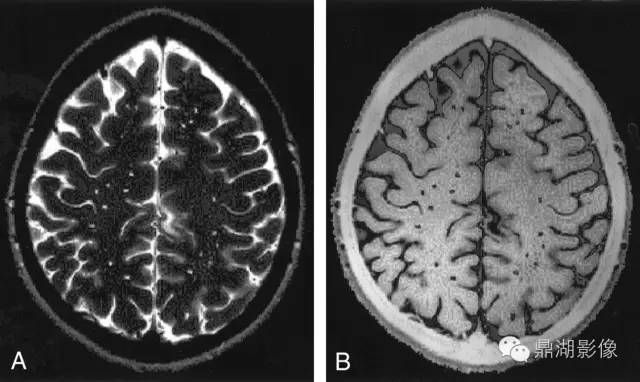

以上两图对照阅读

CMB 在 MRI T2 加权图像上或其他序列图像上表现为小的(通常直径为 2 ~ 5mm,有时可达10 mm)散在信号,对磁化效应敏感 ;但在 CT、FLAIR 序列和 T1 加权图像上不显示。当 T2 加权图像上可以清晰显示 CMB 时,表现为圆形或卵圆形的同质低信号。在 1.5 T 和 3.0 T 梯度回声序列图像上,CMB 的直径通常为 2 ~ 5 mm,有时可达 10 mm。此外,还可以通过磁敏感加权成像来评估 CMB,对 CMB 与自发性颅内深部少量出血进行鉴别。自发性颅内深部少量出血的范围较大,表现为一个不规则的囊腔,其在 T1 和 T2 加权及FLAIR 序列图像上均可显示。

4.2.5 脑微出血

脑微出血定义为在顺磁敏感的序列如T2加权梯度回波序列或SWI上表现为小的(通常直径为2~5 mm,有时达10 mm)散在低信号,对磁化效应敏感。病灶通常边界清楚、均质,在T2加权梯度回波序列上有高光溢出效应(指影像学上显示的微出血面积比实际含铁血红素沉积面积大)。需要鉴别的可能出现类似病灶的情况有铁和钙沉积、骨、正常血管断面的流空效应、弥漫性轴索损伤等。此外,还要区分小的陈旧性的深部自发性脑出血,其范围相比脑微出血更大,有不规则囊腔,且在T1WI上可见。常用的直观定量脑微出血的方法包括微出血解剖评分量表和观察者脑微出血评分量表。计算机自动分析是近年研究热点,它可以缩短评估时间,减少个体间评估差异。